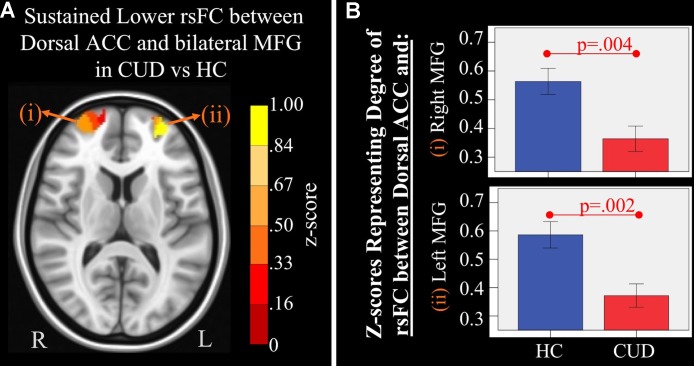

Sustained Group rsFC Differences

There were several significant main effects of group. CUD showed sustained lower rsFC (vs. HC) between the caudal ACC seed and: a) a cluster comprised of the right superior frontal gyrus, dorsal and rostral ACC (f3), b) left middle frontal gyrus (f3), and c) bilateral medial dorsal and anterior thalamic nuclei (f3). CUD also showed sustained lower rsFC (vs. HC) between the dorsal ACC seed and bilateral middle frontal gyrus (f4). All but one effect (the group difference in dorsal ACC rsFC with the left middle frontal gyrus) remained significant when nicotine use and IQ, together with alcohol use, were also covaried in a post hoc analysis. Additionally, ANCOVA results (“Methods,” section Data Denoising) showed that after controlling for the effects of the sum of percent of variance accounted for by noise, differences in all clusters, shown in f3 and f4, were still significant (see F– and P-values in T5).

Table 5: Significant main effect of group. Montreal Neurological Institute (MNI) coordinates of clusters (center of mass) in which resting functional connectivity (rsFC) of regions of interest (ROIs) showed a significant (per-voxel p = .001, cluster p = 0.025) main effect of group (non-treatment-seeking individuals with cannabis use disorder vs. healthy controls). No significant main effects of group were found for other regions of interest. F and significance (Sig) p-values show ANCOVA results controlling for the effects of differences in the sum of percent of variance accounted for by noise.

| ROI | rsFC with: | Hemis-phere | Brod-mann area | x, y, z | F | Sig (p-value) | Cluster size (# voxels) |

|---|---|---|---|---|---|---|---|

| Caudal anterior cingulate cortex (ACC) | Medial dorsal nucleus of the thalamus | Bilateral | — | 1, −18, 5 | 16.27 | .00023 | 1,940 |

| Dorsal and rostral ACC and superior frontal gyrus (SFG) | Bilateral ACC, left SFG | 9, 10, 32 | −1, 39, 16 | 14.40 | .00048 | 6,877 | |

| Medial frontal gyrus | Left | 10 | −30, 54, 16 | 14.13 | .00053 | 684 | |

| Dorsal ACC | Medial frontal gyrus and superior frontal gyrus | LeftRight | 1010 | −29, 59, 1126, 61, 14 | 14.1711.57 | .00052.00151 | 293276 |

Sustained Group rsFC Differences

While another study has reported immediate detrimental effects of cannabis manifested as reductions in rsFC within the default mode network (ref. 52), the current study provides additional supportive evidence of persistent frontal rsFC disruptions (caudal and dorsal ACC) in young adults with CUD. These disruptions could reflect pre-existing liabilities, or it may be that neurotoxic effects of cannabis asymptote persist into young adulthood. Our previous longitudinal fMRI study in adolescents reported that at baseline, rsFC of frontal networks was similar between adolescents with CUD and healthy controls. However, at follow-up, rsFC in individuals with CUD had significantly dropped when compared to HCs (ref. 19), supporting the idea that chronic CUD exerts protracted neurotoxic influences on the intrinsic functional organization of networks that mediate executive control, consistent with previous task-based fMRI studies (ref. 53). Since rsFC represents the functional architecture of brain networks (ref. 54), the quality of rsFC is a measurable manifestation of ongoing state-based brain functional organization that may underlie behavioral alterations (ref. 55, ref. 56). Persistent rsFC alterations of motor and cognitive control networks found in CUD may render them vulnerable to motor disinhibition (i.e., caudal ACC) (ref. 57), poor conflict monitoring, poor decision making, and poor learning (i.e., dorsal ACC) (ref. 29, ref. 58) on a daily basis, which may facilitate further substance misuse.